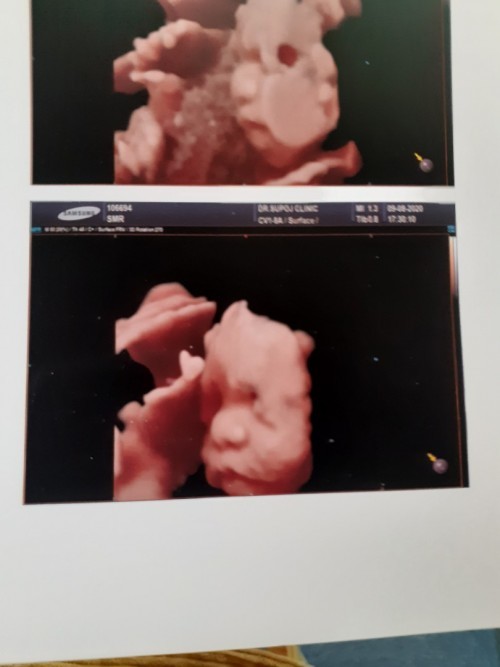

จ้ำม่ำแล้ววว😘😚

ชาวตอน28w❤